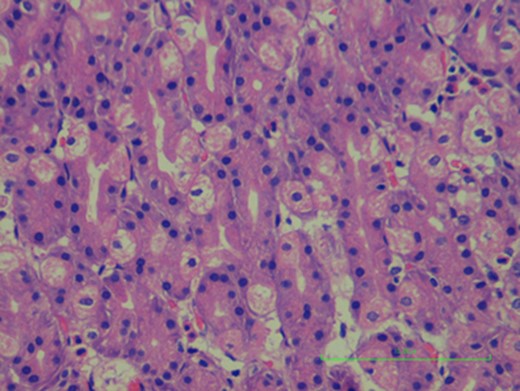

Gastric mucosa in Meckel’s diverticulum, no signs of ulceration where found.

Obstruction due to intussusception or adhesions, ulceration and inflammation (diverticulitis) are complications occurring more frequently among adults [1] (Fig. 3). Bleeding from Meckel’s diverticulum due to ectopic gastric mucosa is the most common clinical presentation, especially in younger patients, but it is rare in the adult population [1]. It is usually painless, which can be slow or even massive, manifesting as anemia or fresh bloody stools. The mechanism of hemorrhage is the ulceration caused by the acid or enzymes secreted from the ectopic digestive mucosa [4]. Intestinal obstruction is the most common complication in adult patients, with incidence rates varying from 22% to just over 50% [3]. The series by Yamaguchi and colleagues, 14 which comprised nearly 50% adults, showed hemorrhage as being less common than obstruction at a rate of almost 5:1 (54%:12%) [3].